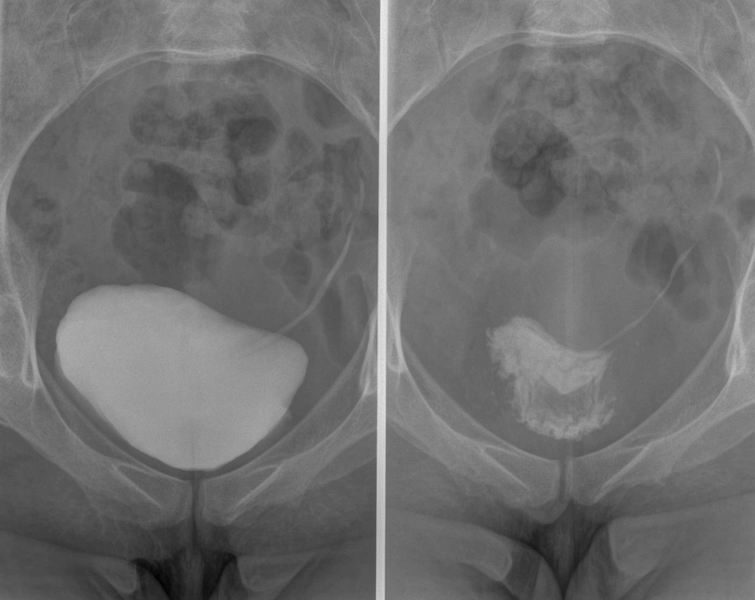

Cystografie